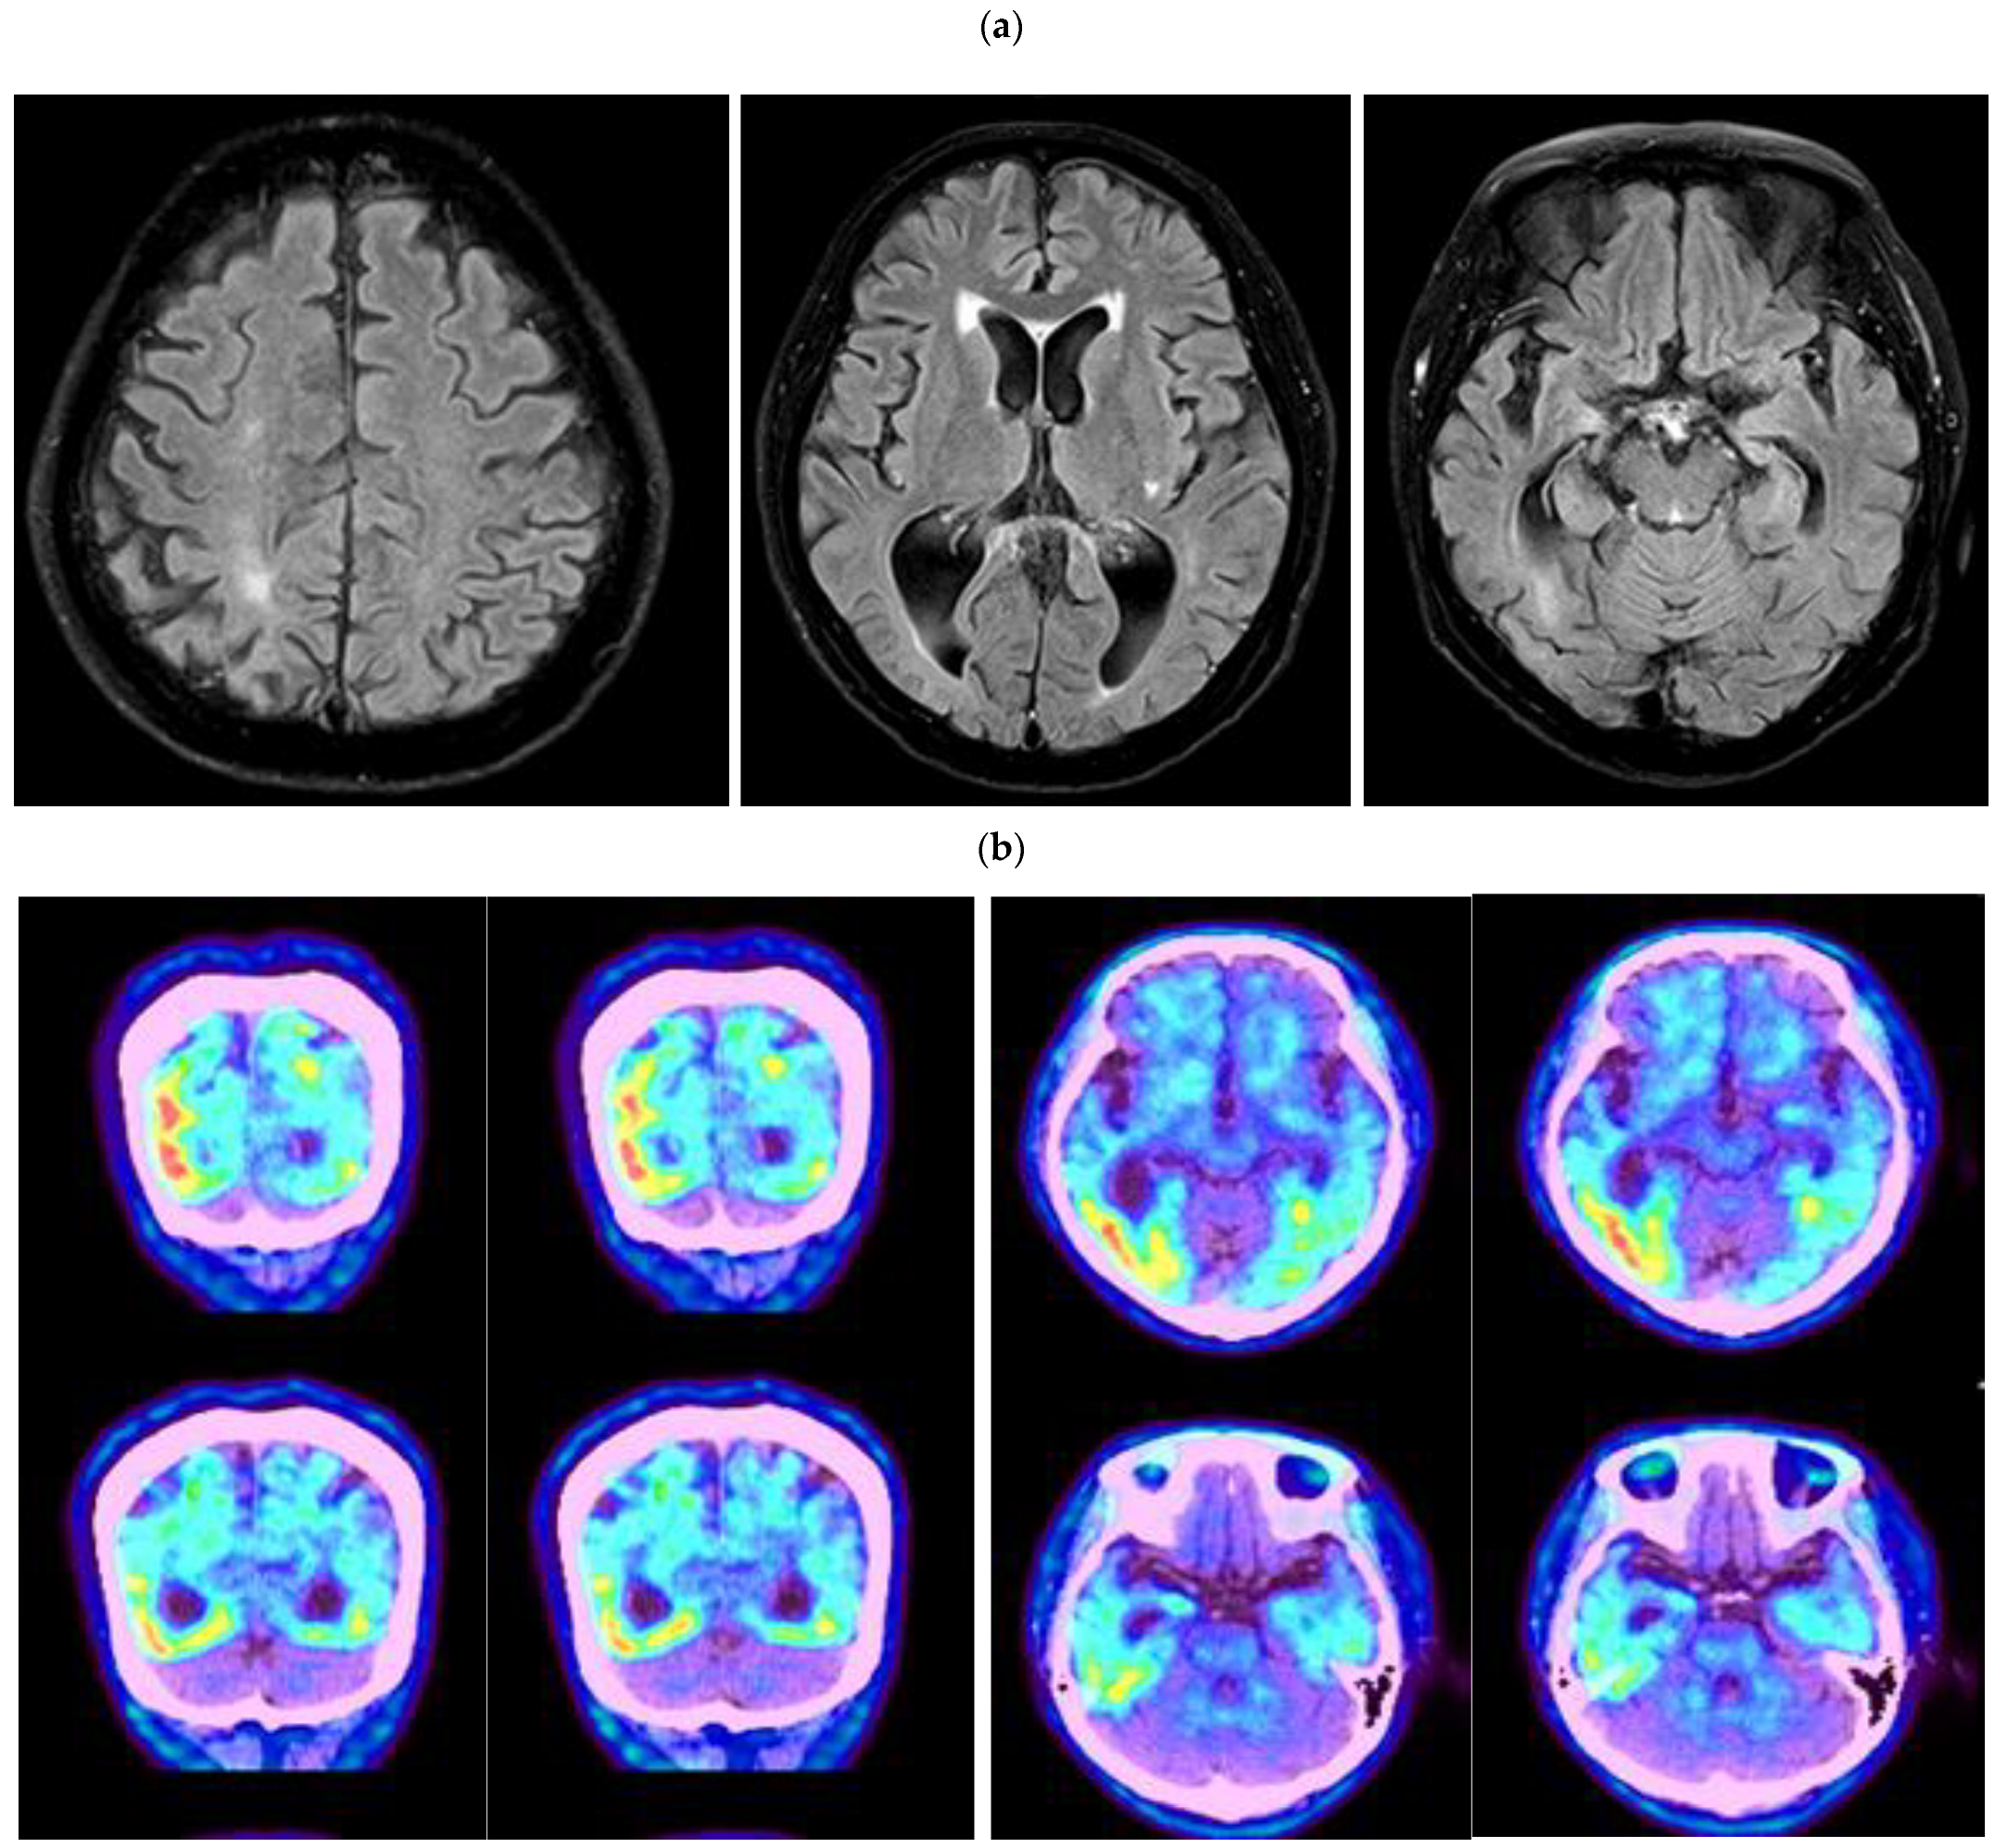

The proband patient was a 56-year-old female patient, who was admitted to the hospital for complaints of gradual memory loss. She was right-handed and a retiree from an office job with a high school diploma. Her cognitive decline began 4 years before the admission in 2021, and her symptoms gradually worsened 3 years before the admission and hospitalization through the outpatient clinic. The patient repeatedly asked the same questions, such as ‘Have you been to the market?’. On the day of the hospital visit, the patient claimed that she came to the hospital by bus, even though her children drove her to the clinic. A year after the first symptom, personality changes appeared. For example, she was often angry, denying what she had done, and lost interest in her hobbies (such as farming), and she became withdrawn from family members and friends. She had difficulties in her daily activities, such as washing, bathing herself, or changing her clothes by herself. However, depression did not appear in the patient. Neurological tests did not reveal any impairment in motor and sensory functions. Her tendon reflexes were normal without any pathological reflexes, and her cerebellar function tests and gait were also normal. From the neuropsychological test, she was able to regurgitate numbers up to three digits with speaking backwards with one digit at a time. In verbal memory, impairment was observed, but the verbal fluency and comprehension were generally good. Overall, she replied to questions with short answers. Tests for apraxia and left-right orientation were normal, but the frontal lobe dysfunction (fist-hand blade-palm disorder) was observed. Spatiotemporal abilities were maintained. Based on the overall neurological diagnose, her motor and sensory were intact without facial palsy or aphasia. Her MMSE score of 10 and GDS score of 5 confirmed her diagnosis after visiting the hospital. Brain fluid-attenuated inversion recovery (FLAIR) MRI showed asymmetric atrophies in the entire brain. Uneven brain loss was most prominent in both temporo-parietal lobes. From the amyloid PET-CT data [14], intense metabolic activity could be seen in the gray matter of both temporo-parietal lobes. Interestingly, the amyloid deposits were asymmetric; they were more prominent in the left side of the temporo-parietal region, compared to the right one (Figure 1a,b). Amyloid deposits were also noticeable in these areas without clear correlations with clinical symptoms.

Figure 1.

(a) Brain MRI of the patient, revealing asymmetric brain atrophies for the entire brain. Brain shrinkage was most prominent in the temporo-parietal lobe. (b) Amyloid PET-CT revealed intense amyloid deposits in the gray matter area asymmetrically. Amyloid deposits were prominent in both parietal and temporal lobes, but they were more prominent in the left temporo-parietal lobes.

The Korean patient with PSEN2 Thr421Met developed memory loss and personality changes at the age of 55. MRI of our patient revealed the asymmetric neural losses and atrophies in the temporo and parietal lobes, which were not typical in EOAD patients. The images from amyloid PET also revealed the asymmetric amyloid deposits in the gray matter of the temporo-parietal lobes, especially in the left lobes. Even though strong amyloid signal was seen in amyloid PET (and elevated levels of CSF-total Tau), the ELISA for CSF- Aβ42 did not reveal significant reduction. Inconsistence in amyloid PET and CSF-Aβ42 levels may be possible. CSF-amyloid positivity may be possible in normal controls (while they are negative for amyloid PET), suggesting that CSF-amyloids may be a more sensitive marker in pre-clinical or early disease stages, while amyloid PET may be a strong marker for more advanced disease stage [20]. Additionally, amyloid PET may be a stronger marker for AD diagnosis, compared to CSF Aβ42 in the case of differential diagnosis of neurodegenerative diseases [21]. AD patients were reported before, who were positive to amyloid PET and CSF-Tau, but no reduction was observed in CSF-amyloid levels. One of the explanations could be that CSF-amyloid only reflects the soluble pool of amyloid peptides, while amyloid PET may represent the fibrillar amyloid aggregations. Moreover, CSF Aβ42 and amyloid PET could be possibly related independently and differentially to the other, non-amyloid types of AD pathology (such as CSF-Tau, hippocampal atrophy, APOE E4 allele, or reduced cerebral blood flow) [22,23]. CSF amyloid may be strongly correlated with APOE E4 allele, while PET positivity may be associated with CSF-Tau positivity or Alzheimer’s Disease Assessment Scale-cognitive subscale (ADAS-cog). The strong relationship between Tau positivity and ADAS-cog also confirmed that amyloid PET may be a more effective diagnostic marker in later disease stages, compared to CSF-amyloid. PET-positivity and CSF Aβ42 negativity may also suggest that fibrillar amyloid or short amyloids, such as Aβ40, should also be considered as potential CSF markers [20,21,22,23]. Since our patient had APOE E3/3 genotype, other genetic risk factors may contribute strongly to the disease onset. Table 1 presents the comparison of the Korean and Japanese patients with PSEN2 Thr421Met mutation.